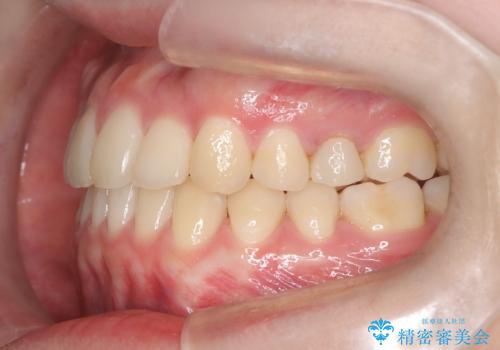

- 前歯のガタツキが気になるとのことで来院されました。

ワイヤー矯正とインビザライン矯正を併用することによって、治療期間の短縮と、より良い仕上がりを目指す治療を選択することとしました。

インビザライン(アライナー)矯正とワイヤー矯正のそれぞれの利点を生かした治療を行い、綺麗な歯並びになりました。